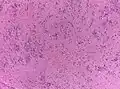

- Субэпендимома (синонимы: субэпендимарная узловая астроцитома, эпендимоастроцитома, эпендимоглиома) развивается из субэпендимарной глии и состоит из островков мономорфных эпендимарных клеток, которые располагаются в густом окружении глиальных бесклеточных волокон. Субэпендимома имеет форму узла и располагается внутри желудочковой системы головного мозга.

Субэпендимома